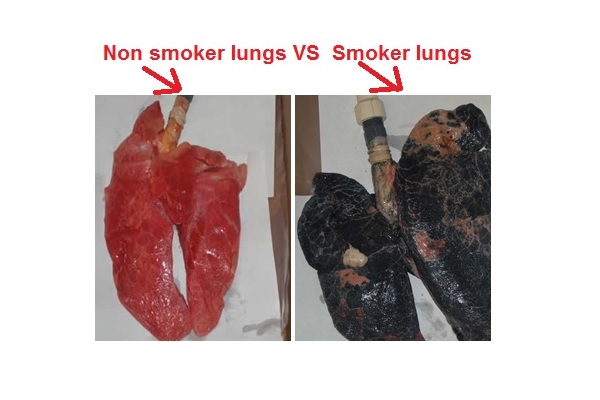

به گزارش گروه سلامت عصر ایران به نقل از "نیو هلث ادوایزر"، اقدام های مختلفی در راستای تشویق افراد سیگاری به ترک آن در سراسر جهان انجام می شوند و حتی برخی از آنها ممنوع کردن استفاده از تنباکو را هدف قرار داده اند. اما یکی از مواردی که در کمپین های مختلف مبارزه با سیگار به چشم می آید تصاویر ریه افراد سیگاری در کنار ریه افراد غیر سیگاری است که نشان می دهند این کار تا چه اندازه می تواند به ریه ها آسیب وارد کند.

تصاویر ریه افراد سیگاری

تصاویری که در ادامه ارائه شده اند ممکن است برای برخی افراد ناخوشایند باشند. اما اگر سیگار می کشید شاید مشاهده این تصاویر عزمتان برای ترک آن را جزمتر سازد.

مقایسه ریه سالم و ریه فرد سیگاری

ریه سالم قرمز رنگ است. پس از سیگار کشیدن برای چندین سال، مواد شیمیایی سیگار در ریه ها رسوب کرده و آن را به رنگ سیاه در می آورند. ریه های انسان به عنوان یک فیلتر عمل کرده و از بدن در برابر مواد شیمیایی مضر محافظت می کنند. به جای ورود مواد شیمیایی به مسیرهای هوایی، ریه های شما آنها را جذب می کنند. این مواد شیمیایی می توانند موجب بروز سرطان در ریه شوند.